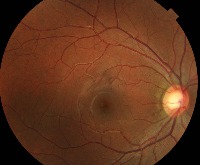

Classes (69)

0.0.Normal

0.1.Tessellated fundus

0.2.Large optic cup

0.3.DR1

1.0.DR2

1.1.DR3

10.0.Possible glaucoma

10.1.Optic atrophy

11.Severe hypertensive retinopathy

12.Disc swelling and elevation

13.Dragged Disc

14.Congenital disc abnormality

15.0.Retinitis pigmentosa

16

17

18

19

2

2.0.BRVO

2.1.CRVO

3.RAO

4.Rhegmatogenous RD

5.0.CSCR

5.1.VKH disease

6.Maculopathy

7.ERM

8.MH

9.Pathological myopia